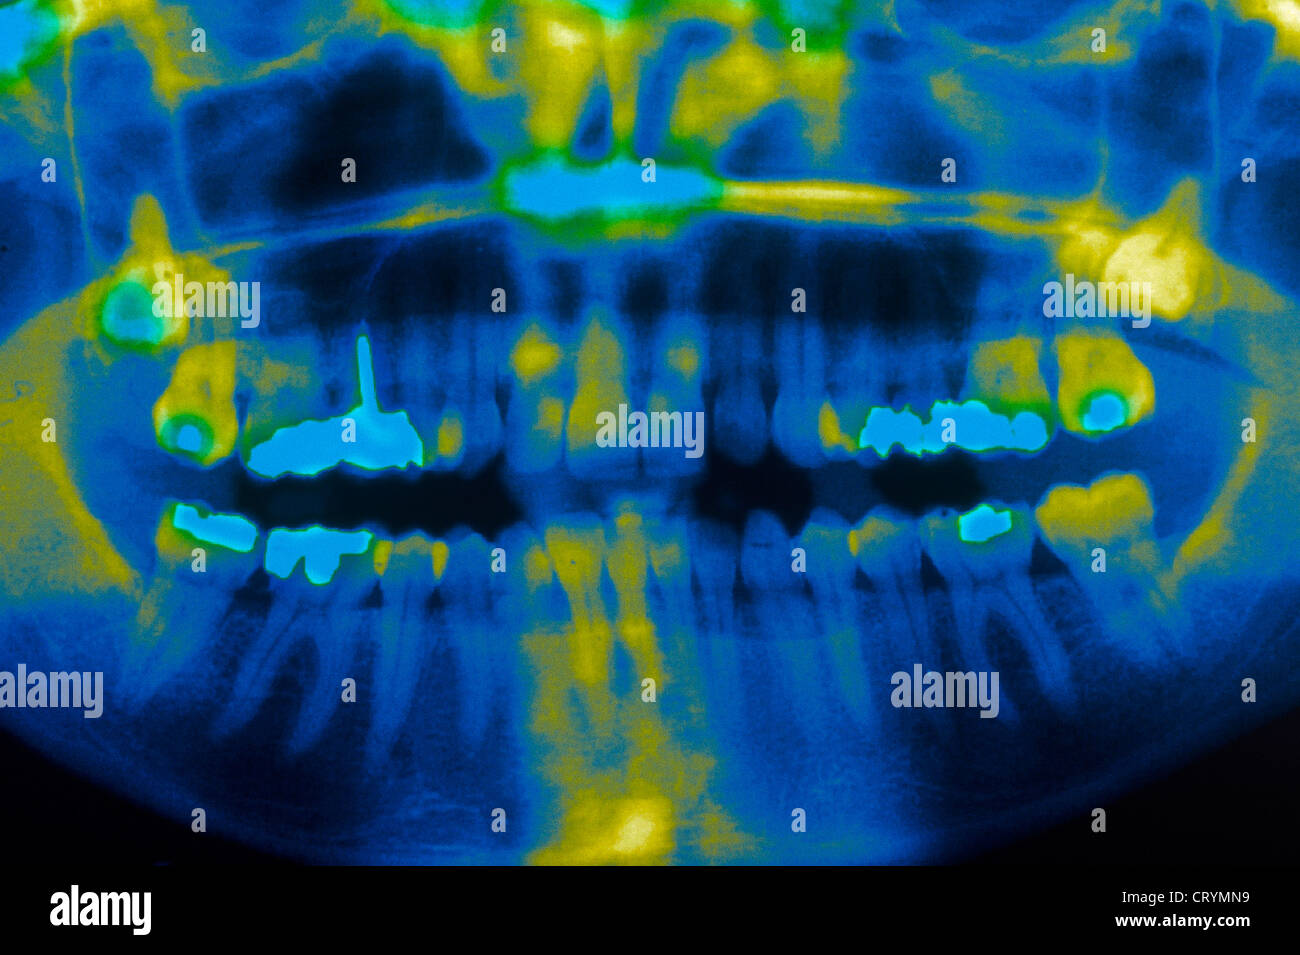

Wisdom Teeth Eruption, Panoral X-ray - Stock Image - C013/1068

Panoramic Dental X-ray With Superior Upper Wisdom Tooth (eight Tooth

www.alamy.comtooth

www.alamy.comtooth